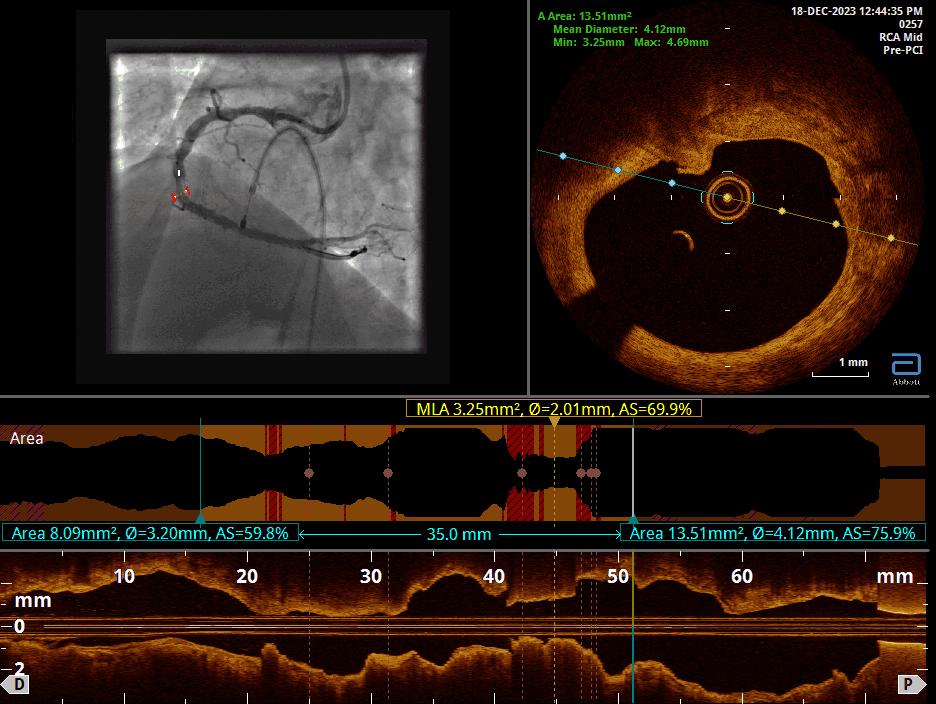

We proceeded with Percutaneous Transluminal Coronary Angioplasty (PTCA) of the Right Coronary Artery (RCA), utilizing ROTAPRO SUPPORT due to the calcified nature of the lesion. The CTO was successfully crossed using a Conquest Pro wire. Intravascular imaging, specifically Optical Coherence Tomography (OCT), confirmed the presence of multiple calcified nodules, highlighting the difficulty of the case.A 1.5 Rotapro was used for preparation.